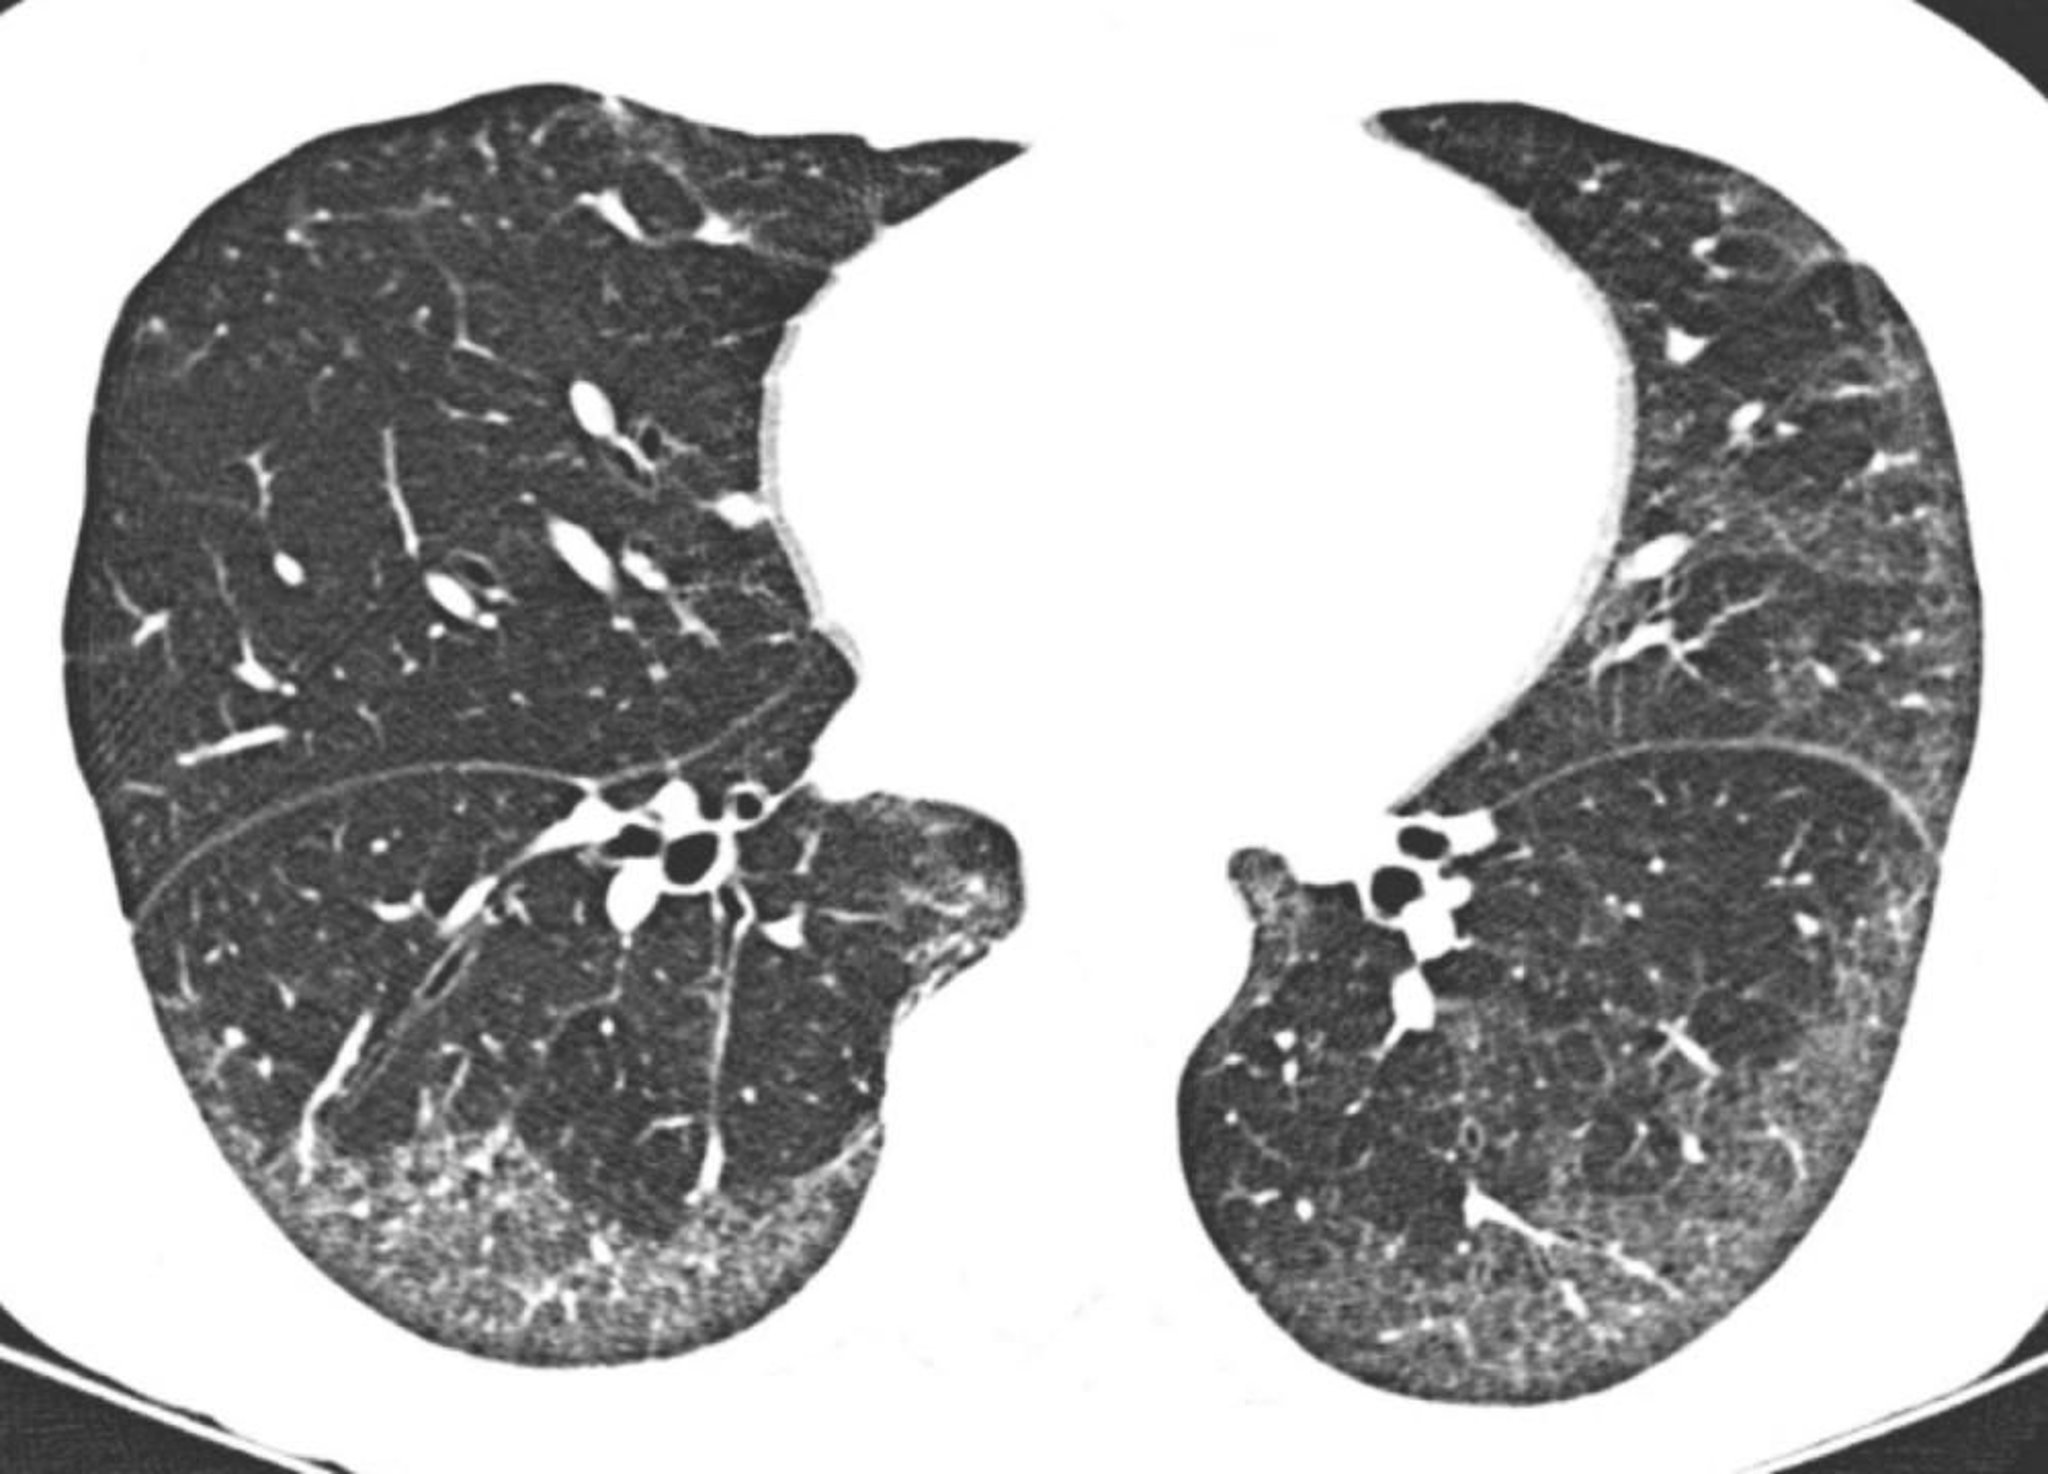

Idiopathic Nonspecific Interstitial Pneumonia

High-resolution CT shows predominantly subpleural and basilar ground-glass opacities. The relative sparing of the lung directly beneath the pleural surfaces is typical in nonspecific interstitial pneumonia.

Image courtesy of Harold R. Collard, MD.